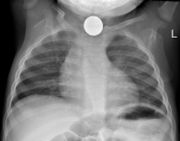

Prior to undertaking endoscopy, attempts should be made to locate the foreign body with x-rays or other non-invasive techniques. For radio-opaque objects, x-rays of the neck, chest and abdomen can be used to locate the foreign body and assist endoscopy. Alternative approaches, including the use of metal detectors, have also been described.

X-rays are also useful for identifying the type of foreign body ingested and complications of foreign body ingestion, including mediastinitis and perforation of the esophagus.